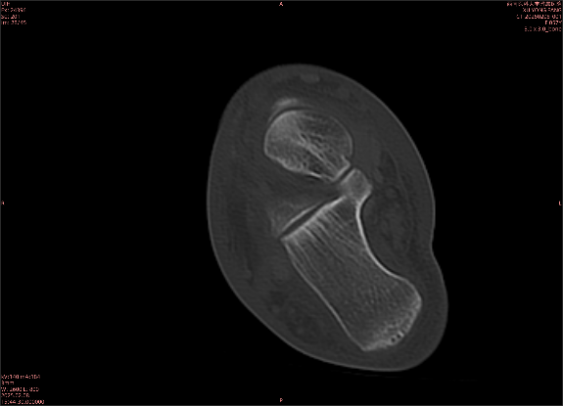

舉例圖像

圖1

專業(yè)解釋看不懂沒關(guān)系,大家看圖1和圖2就可以了,這是同一個(gè)患者跟骨的磁共振和CT圖像,圖1的紅色箭頭指示的黑線就是磁共振圖像顯示的骨折線,一目了然。而對(duì)比圖2的CT圖像上并未顯示異常。

這下大家明白了吧,如果懷疑隱匿性骨折優(yōu)先選擇磁共振檢查